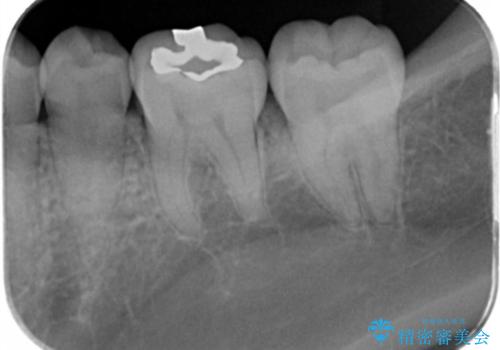

白い歯にしたいとの事だったのでセラミックインレー(e-maxインレー)にて治療しました。

- e-maxインレー 7.7万円 費用は治療当時の料金となります

セラミックの詰め物は銀の詰め物に比べて適合がよく、虫歯の再発のリスクが少なくなります。白い詰め物が入り大変満足して頂けました。